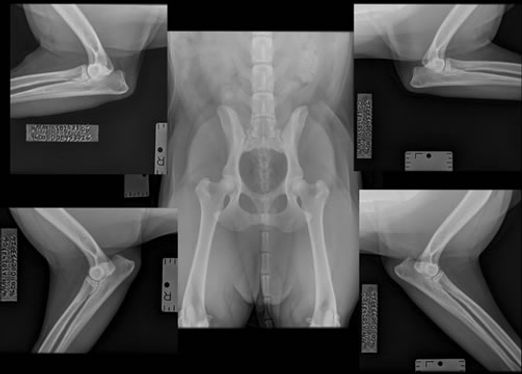

There is no regulation for health testing dogs for breeding and registering with the UK Kennel Club. KC registration is not an indicator of the health or quality of a dog as even puppy farmers can still KC register pups. However, most show and work breeders, and those who are linked to them, all health test to what the breed calls for. In Rottweilers the tests suggested are the LEMP, JLPP, XLMTM, NAD, DM Exon 2, Hips and Elbows.